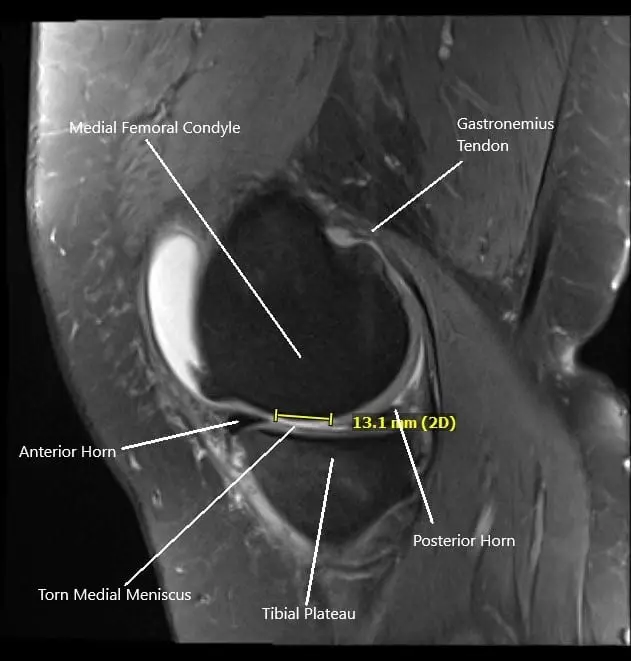

Intraoperative fluoroscopic image of subchondroplasty.

Now, the attention was moved to the fixation of the stress fracture of the medial tibial plateau. The cannula was entered from the subchondroplasty set medially under C-arm control about a centimeter below the joint surface. It was inserted in an anterolateral direction.

The cannula was checked in AP and lateral view and found to be in adequate position. The subchondroplasty calcium phosphate cement was inserted using 1 cc syringes. Five syringes were used.

The cement could be seen filling up the medial tibial plateau region superiorly, superior to the cannula. Ten minutes were given for the cement to set. The cannula was removed. The final picture was taken and saved.